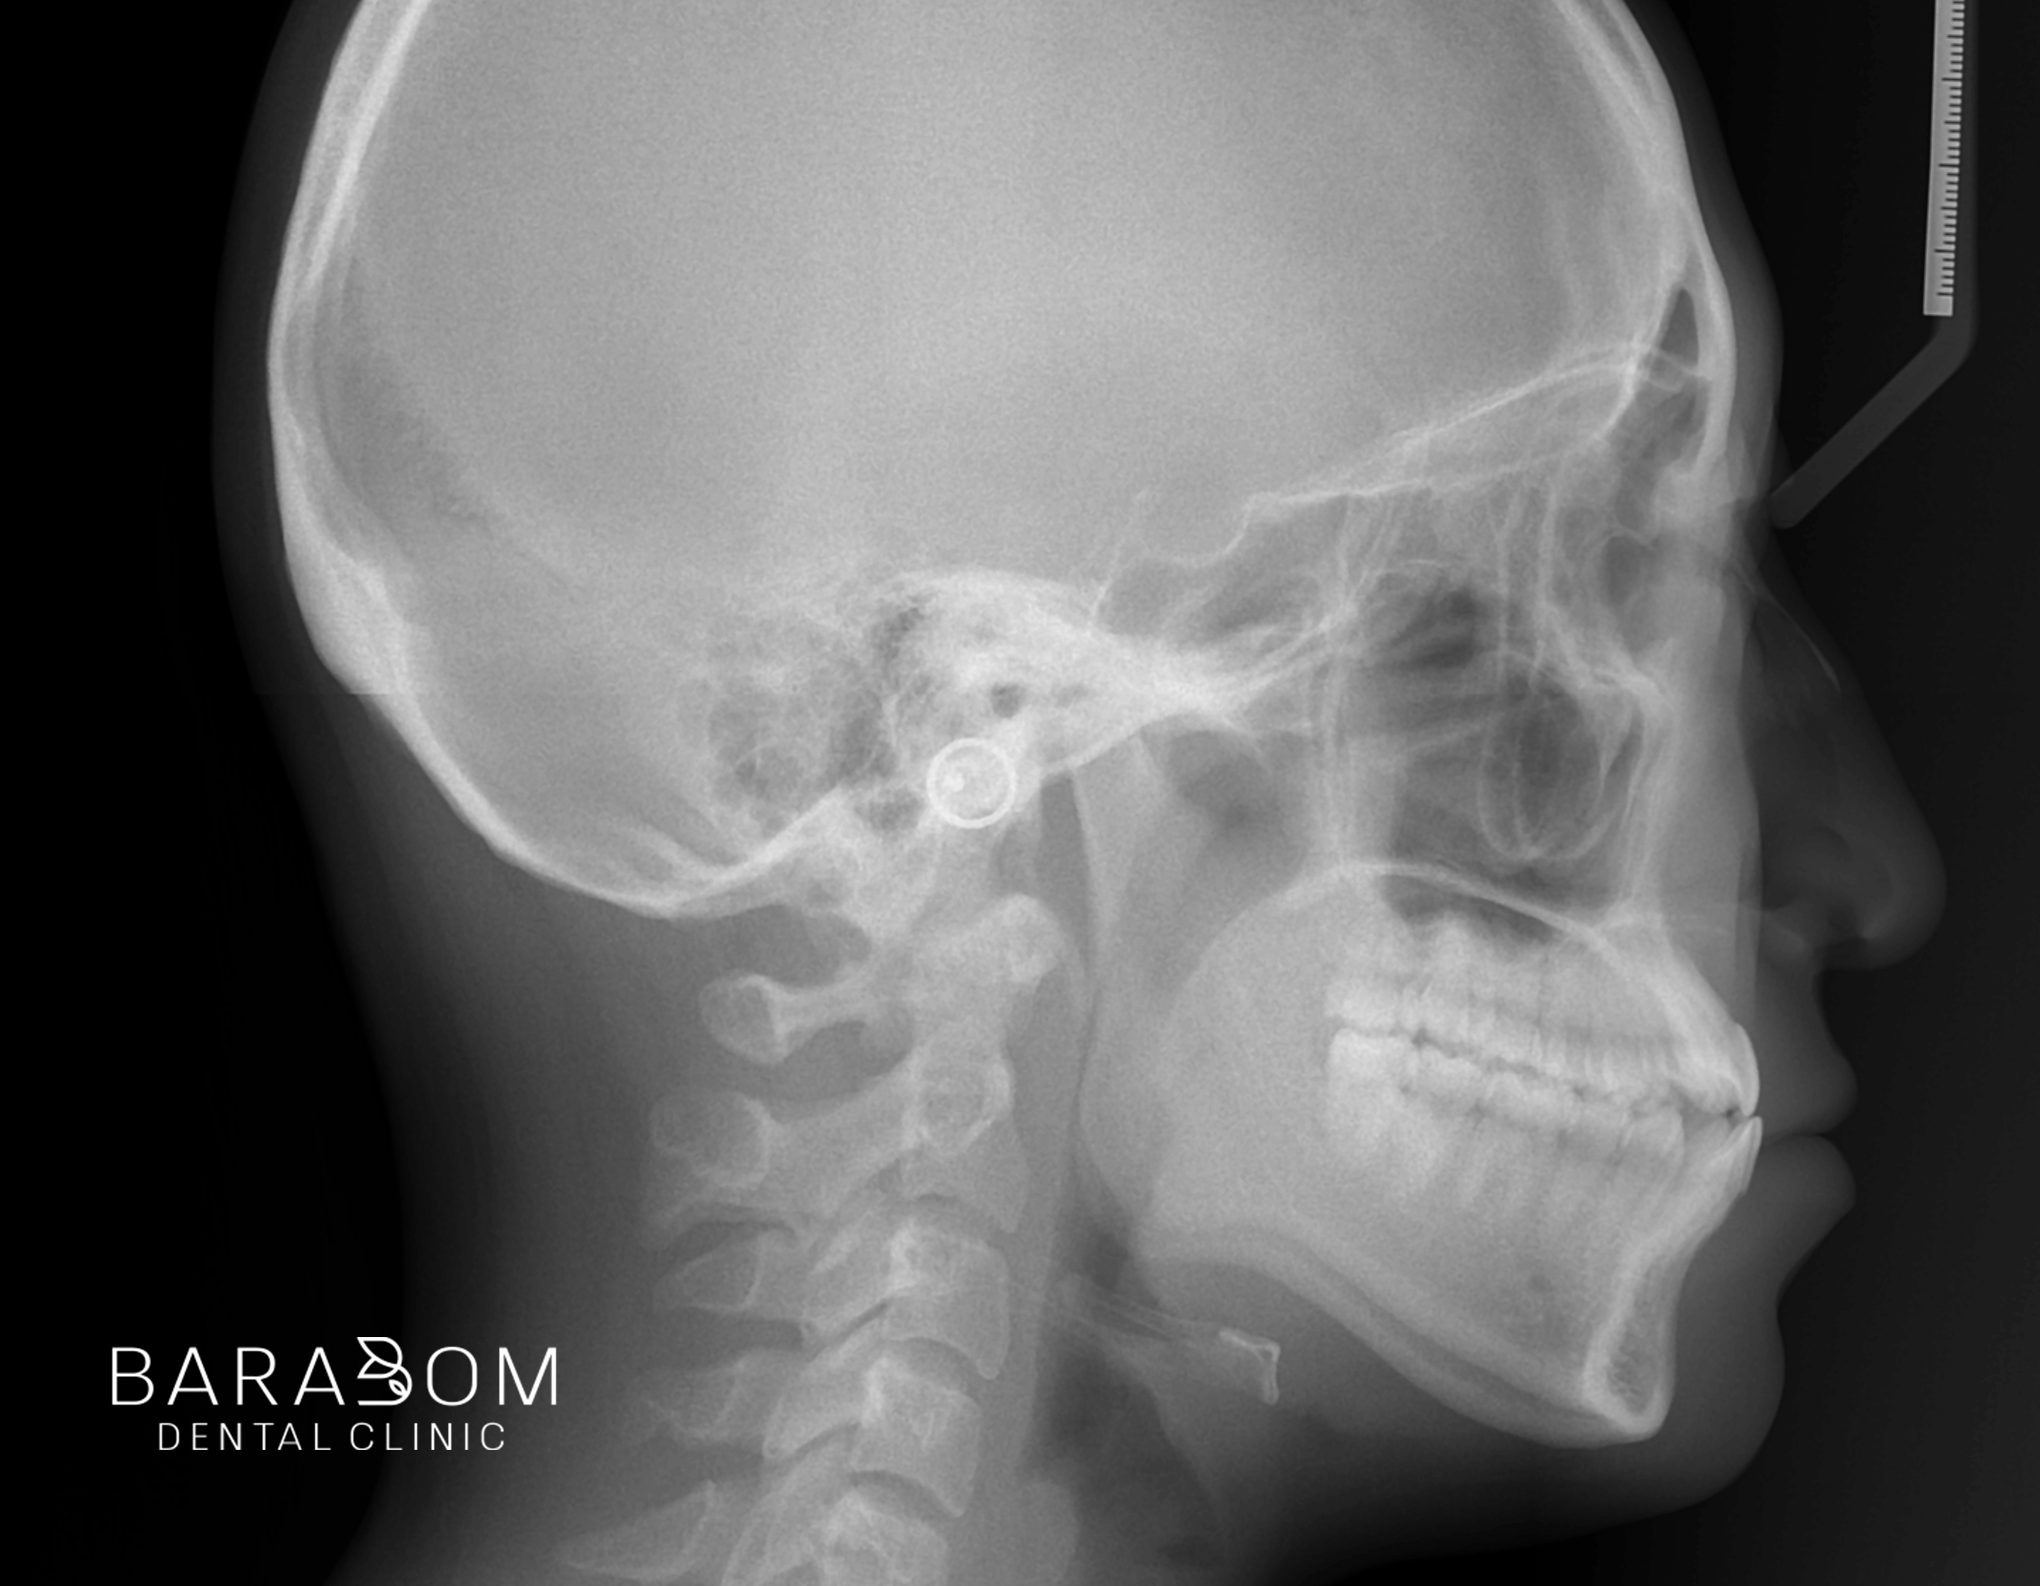

엑스레이 사진을 통해

4군데 모두 사랑니가 있는 것이

확인되는데요,

아랫턱 전체 치열을 후방으로

이동하기 위해서는 발치가 필요합니다.

그래야 뒤로 움직일 수 있는

공간이 충분히 확보됩니다.